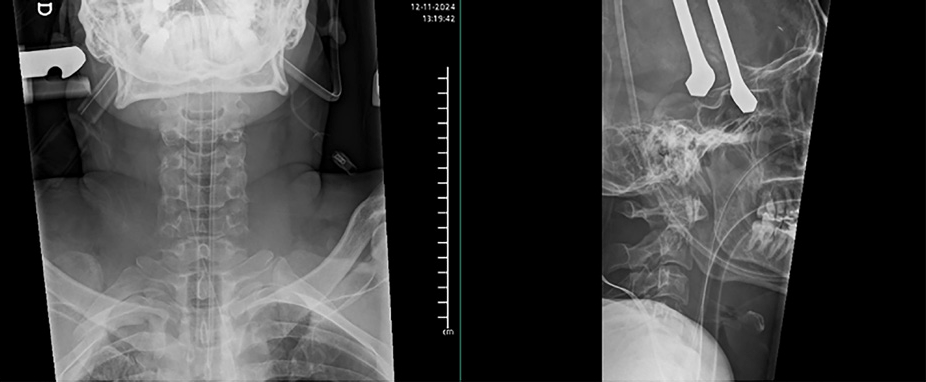

Ingresa en UCI, donde permanece estable HD. Se traslada a su hospital de referencia al día siguiente para manejo definitivo, donde finalmente se realiza abordaje cervical posterior y fijación C1-C2 con tornillos de C1 y C2 a masas laterales, mediante TAC intraoperatorio, sin incidencias.

Entre las opciones quirúrgicas encontramos la fijación con tornillos por abordaje anterior, en fracturas IIA y IIC (Roy Camille), que puede combinarse con cifoplastia. Otra opción es la fusión vía anterior C1-C2, en combinación con la técnica anterior cuando es insuficiente. En cuanto a la vía posterior, se puede hacer una fusión C1-C2, introduciendo tornillos en ambas masas de C2 y C1 o una fusión transarticular con tornillos desde C2 orientados hacia las masas de C1. Esta última técnica está contraindicada en caso de anomalías anatómicas de la arteria vertebral anterior. La tasa de complicaciones entre ambos abordajes es similar, aunque la tasa de fusión es mayor en la vía posterior.